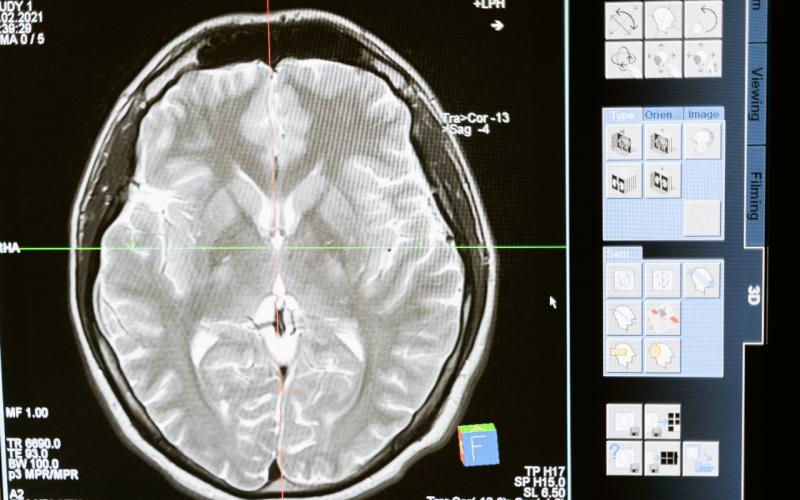

Para obtener el diagnóstico se realiza una evaluación multidisciplinaria integrada por neurología, neurocirugía, ortopedia y médico pediatra; además, se necesitan imágenes computarizadas y la resonancia magnética cerebral, esta última es la ideal.